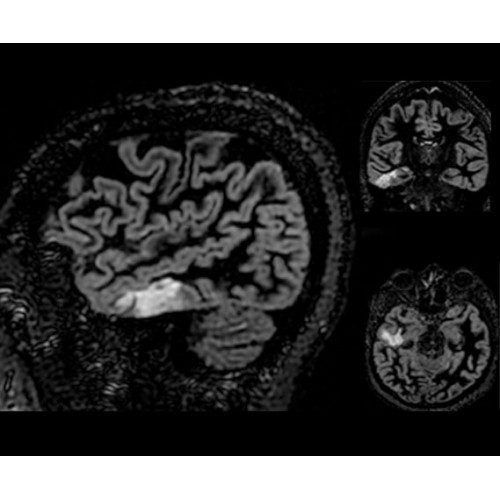

SIGNA Architect 3.0T — это новейший МРТ аппарат компании GE, который предлагает высочайший уровень производительности — в системе 128 приемных каналов, 48 канальная катушка головы, полный спектр клинических возможностей. Высокий уровень комфорта пациента обеспечивают такие особенности как отсоединяемый стол, положение пациента «ногами вперед» для всех видов исследований, SilentWorks — бесшумное и MAGIC — быстрое сканирование.

Теперь возможности МРТ поражают еще больше благодаря ультрасовременным решениям для визуализации с SIGNA Architect 3.0 Тл, объединяющей новейшие достижения в области МР-технологий и интуитивно понятный интерфейс. Система SIGNA Architect, разработанная на базе новой платформы SIGNA Works, представляет собой гармоничное сочетание дизайна и функциональности. Каждый элемент системы направлен на повышение производительности, эффективности клинической практики, финансовых показателей, а также комфорта и безопасности пациента.

Поле обзора 50x50x50 см и апертура шириной 70 см позволят достоверно визуализировать сложные анатомические области для пациентов с крупным телосложением, например, плечи и бедра. Феноменальная однородность системы SIGNA Architect обеспечивает наиболее широкое поле обзора с улучшенными характеристиками градиентов. Ничто не останется незамеченным.

• NeuroWorks — универсальное решение для визуализации анатомии головного мозга, позвоночника, сосудов и периферических нервов с четкой дифференциацией тканей.

• 48-канальная катушка TDI для головы, входящая в базовую комплектацию SIGNA Architect, обеспечивает феноменальную производительность с учетом особенностей каждого пациента. Благодаря гибкому и универсальному дизайну, высокому соотношению сигнал/шум и передовым технологиям визуализации, таким как HyperWorks, учитываются потребности подавляющего большинства пациентов.